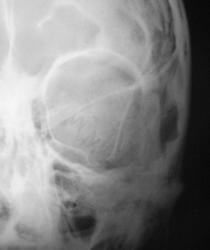

Пациент в ургентном порядке, после ДТП был доставлен в ЦРБ в ночное время. Был вызван "ургентный лаборант" для рентгенографии черепа. Пациент без сознания. С учетом состояния пациента рентгенография произведена в нестандартных проекциях - "задняя прямая".

Линейный перелом костей крыши черепа, возможно с переходом на основание. Вот только не понятно есть или нет импрессионный перелом височной кости, а ещё больше похоже на наличие пневмоцефалии.

А что скажите по поводу пирамидки и орбиты справа?

Контуры пирамиды чёткие, а вот латеральная стенка орбиты возможно сломана. Он был отправлен в ОКБ?

Линейный перелом с переходом на основание - дно средней черепной ямки. Сейчас вопрос о пирамидке и орбите не принципиальный. Главный вопрос нет ли внутричерпной гематомы. Если больной выйдет из тяжелого состояние, и встанут экспертные вопросы можно сделать Стенверс при потере слуха, Майер при кровотечении из уха. Насчет стенки орбиты - наличие перелома сомнительно, явно не видно. Также можно доснять при улучшении состояния. Судя по всему это молодой человек. Сколько лет?

Вижу только линию перелома височной и теменной костей, высока вероятность перехода на основание, остальное - домыслы и сомнения.